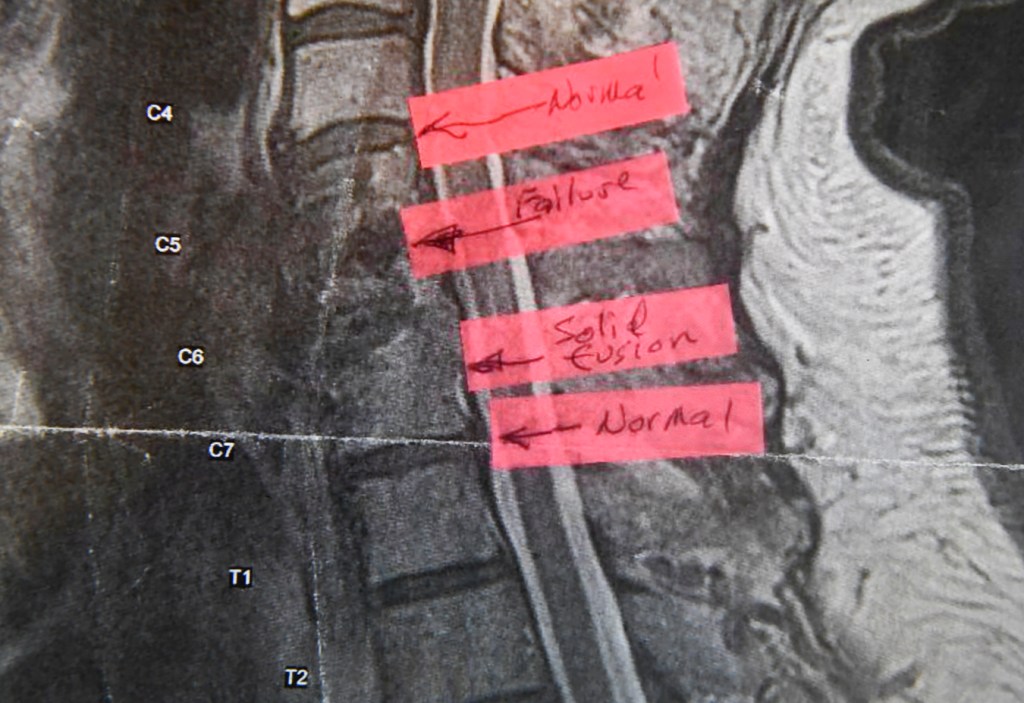

John Saltis is suing spinal device company NuVasive over its handling of his complaint that a screw holding his spinal implant in place snapped in May 2016, about 17 months after his operation.

Saltis, 68, was two hours into his workday as a toolmaker at General Electric in Rutland, Vermont, when he felt sharp pain in his neck and shoulder, bad enough to send him to the hospital emergency room. A few days later, X-rays revealed the screw had broken and, according to Saltis, fractured vertebrae in the process.

Saltis said the San Diego-based device company told the FDA the incident caused no harm. But Saltis said he has lingering numbness and pain in his right hand. As a result, he said, his lifestyle has “changed dramatically.” He sold his motorcycle and stopped biking and now relies on his left hand for simple tasks like opening doors and shaking hands — even plucking chips out of a bag.

In 2019, Saltis sued NuVasive without a lawyer, hoping to show the $600 screw was defective. In a court filing, NuVasive said Saltis is arguing “the screw is defective because it broke.” That’s not good enough, according to NuVasive, which argues that Saltis must show the screw was “unreasonably dangerous” to press his claim. In late June, a federal judge agreed and dismissed the suit, though she allowed Saltis to amend his complaint, which he is pursuing. The case is pending.

“I was pain-free for a few months and would have stayed that way if the screw hadn’t broken,” Saltis said. “This can change somebody’s life completely.”